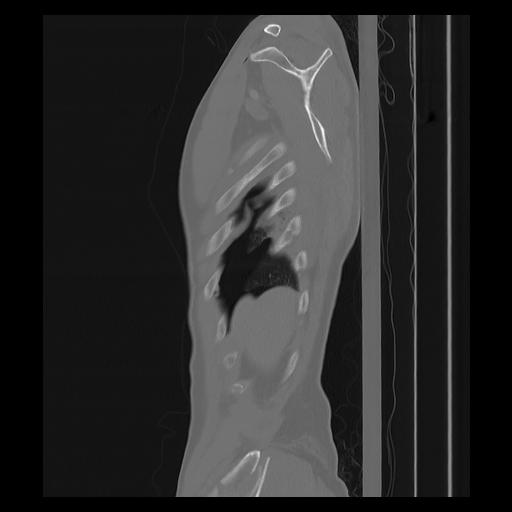

33 PULMON,CE,Sagittal,3.000,PULMON,Sagittal,